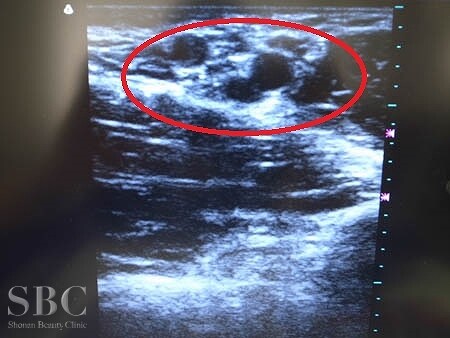

No.95890【わきが・多汗症】湘南美容外科全ドクターの中で最もワキのニオイの手術件数が多い!あの有名な根こそぎ竹田先生の劇的ビフォーアフター!〜ワキのニオイは消し去るもの!根こそぎベイザーシェービング法・右ワキ術中超音波画像〜